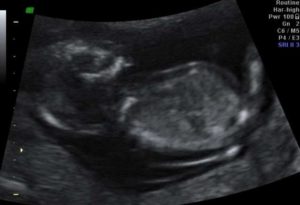

Özellikle teknolojilerin gelişmesiyle beraber tıp alanında gözle görülür değişimler yaşanmıştır. Çoğu zaman teknolojinin ulaşmadığı noktalarda bebeğin sağlık durumu anlaşılamadığından bebeklerin engelli ve hastalıklı doğması muhtemel olmaktadır. ancak günümüzde gelişen ultrason adlı cihaz bu sıkıntıları tamamen ortadan kaldırmakta ve bebeğin durumu ile ilgili an be an istenirse görüntü alınabilmektedir.

Bu sebeple dilediğiniz kadar ultrason cihazında bebeğinizi kontrol edin bebeğe herhangi bir zararı dokunmamaktadır. Ayrıca olası bebek rahatsızlıklarında erkenden önlem alarak bu durumun önüne geçilmekte ve hem anne sağlığını hem de bebeğin sağlığını korumaktadır. Özellikle bebekte oluşabilecek bazı önemli anormallikler de anne sağlığı da ciddi biçimde etkilenmekte ve hayati tehlikelere varabilmektedir. Bu sebeple bebeğin kontrolü her zaman için çok fazla önem arz etmektedir anne adayı gebelik durumundan şüphelendiği anda radyoloji uzmanına başvurmalıdır.

Çünkü bebeğin anne karnına düştüğü günden itibaren sağlıklı gelişmesi çok önemlidir. Belirtelim ki, bir annenin sağlığı her zaman için bebeğin sağlığından daha önemlidir. Bu sebeple bu kontrollere gebeliğin ilk günlerinden itibaren sıklıkla gitmek gerekmektedir. Ayrıca gebelik için bazı önemli haftalarda bulunmaktadır. Bu haftalarda da sık sık kadın doğum uzmanlarına gidilmek suretiyle bebeğin sağlık ve gelişim durumu hakkında bilgi alınması gerekir. Yani bir anne adayı bebeğinde gelişimler de sıklıkla doktorun gözetimi altında bulunmalıdır. Bu sebeple bebeğin gelişimi radyoloji uzmanı tarafından yapılan ultrason cihazında görüntülenebilir. Bebeğin boyu, kilosu, cinsiyeti, amnion sıvısı miktarı, ense kalınlığı, kollarda ve bacaklardaki gelişmeler, yüzün ve vücudun oturması, kemik gelişimi ölçümü bu cihaz sayesinde rahatlıkla yapılabilmekte ve içinde olunduğu haftadaki normal gelişimi ne derece sağlıklı ve doğru ilerlediği sürekli gözlemlenmektedir. Bu cihaz ile birlikte artık bebekte oluşan her türlü gelişim rahatlıkla izlenmekte ve aile üyelerine bu konuda her türlü bilgi verilmektedir.